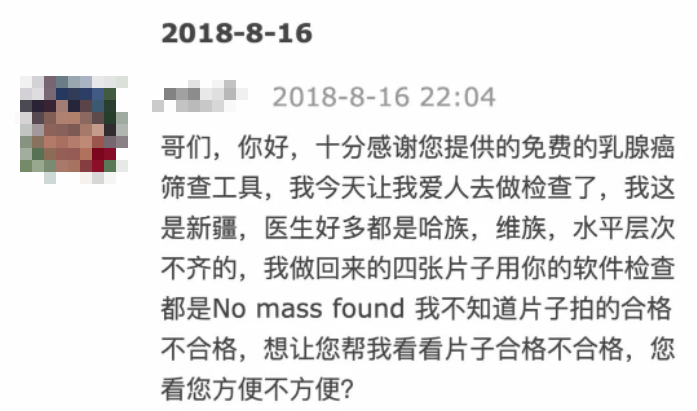

他说,由于后台不保存数据,所以并不清楚具体有多少人使用过。

但在那段时间,他收到了很多患者的感谢邮件,不少都来自国人。

而且,用户真的用网站检查出了肿瘤,尤其对于医疗资源紧张地区的人们,相当于从死神手里抢下时间。

第一位哥们照片搞错了,

重新检测后发现了肿瘤 ▼